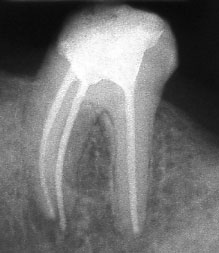

При добре проведено ендодонтско лечение кореновият канал е запълнен точно до стеснението, разположено на 1 - 1.5 мм. от края на канала - т.нар. физиологично стеснение. Не бива да остава незапълнена част от канала. Много често се получава припресване на канлопълнежното средство извън канал на зъба, в тъканите около корена.

Рентгенографии на добре пролекувани зъби

Винаги е необходимо лекуващият да се стреми към този резултат: